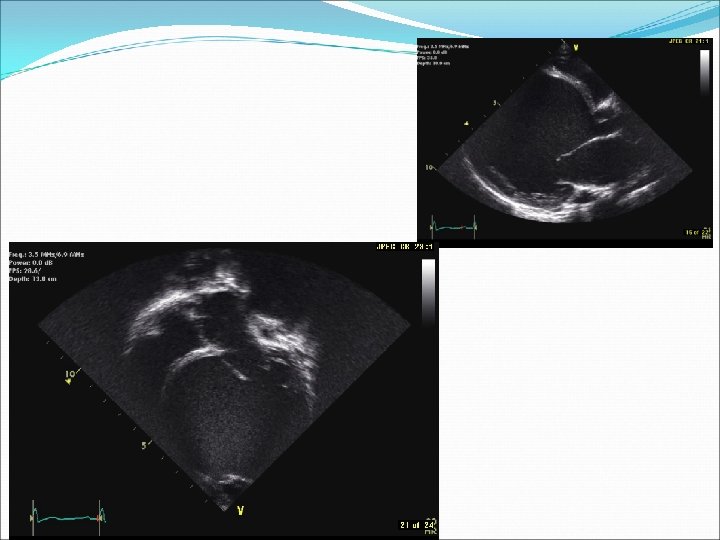

�Ekokardiyografi sol ventrikül sistolik ve diyastolik fonksiyonlarını gösteren kolay ve en ucuz metottur. �Ayrıca ekokardiyografi ile kapak hastalıkları, sol ventrikül duvar kalınlığı, kalp odacıklarının boyutları, perikardiyal hastalık varlığı da değerlendirilebilir.

�KKY, genişlemiş kalp odacıkları ve/veya kapak yetmezlikleri ve/veya bozulmuş sol ventrikül fonksiyonu (azalmış kısalma fraksiyonu, azalmış ejeksiyon fraksiyonu) izlenir. �Ayrıca ekokardiyografi, tedaviye yanıtın takibinde de yardımcı bir tetkik olma özelliğini korumaktadır.